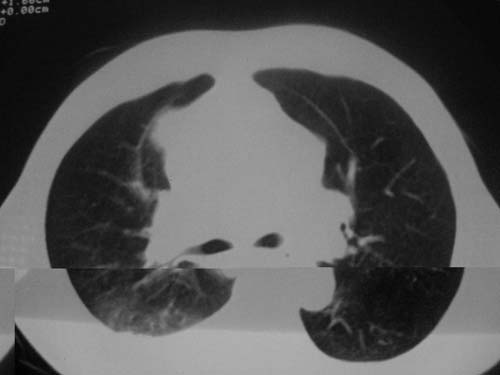

以下是引用科室第一人在2010-3-25 20:30:00的发言:[br]1:纵膈肿瘤性病变,恶性胸腺瘤可能性大伴纵膈右肺门淋巴结转移,右侧胸腔积液。[br]2:右侧肺门肿瘤性病变,纵膈淋巴结转移,右侧胸腔积液。右下叶转移。

以下是引用子期在2010-3-25 21:00:00的发言:[br]先考虑右中央型肺癌伴转移。

以下是引用江广1996在2010-3-25 22:49:00的发言:[br]通常肺癌向纵隔转移多见,纵隔肿瘤向肺内转移少见(有的表现为向肺内侵润)。本例以一元论考虑:右中心型肺癌并纵隔淋巴等多处转移。[br][br][本贴已被 江广1996 于 2010-3-25 22:50:07 修改过]

以下是引用yangyudong333在2010-3-26 6:43:00的发言:[br]“冰冻纵膈”,考虑纵膈淋巴瘤伴肺内及胸膜侵润。